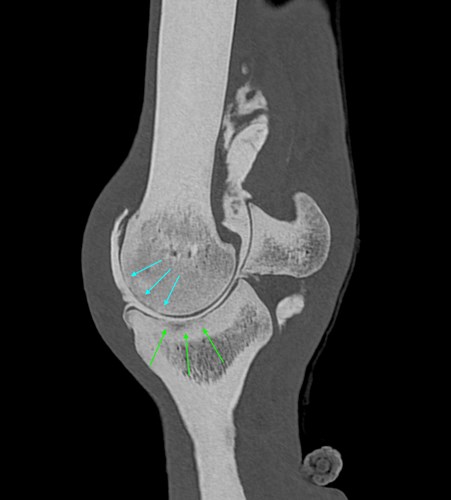

Getting a clearer picture - Understanding your horse through advanced imaging

• Firstly, learn how advanced diagnostic imaging can help us get a clearer picture of your horse's condition

• Followed by a tour around the four corners of our fantastic diagnostic imaging department getting a behind the scenes look at what goes on and how each of the modalities work.